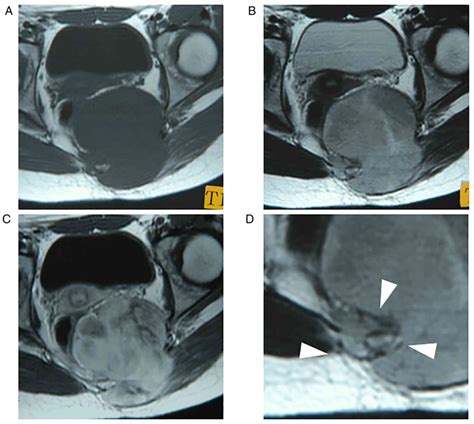

Diagnosing a spindle cell tumor typically involves a combination of imaging tests, such as X-rays, CT scans, and MRIs, as well as a biopsy to examine the tissue under a microscope. The biopsy is crucial for determining the specific type of spindle cell tumor and its grade, which indicates how aggressive the tumor is likely to be.

• Imaging tests, such as CT scans or MRIs